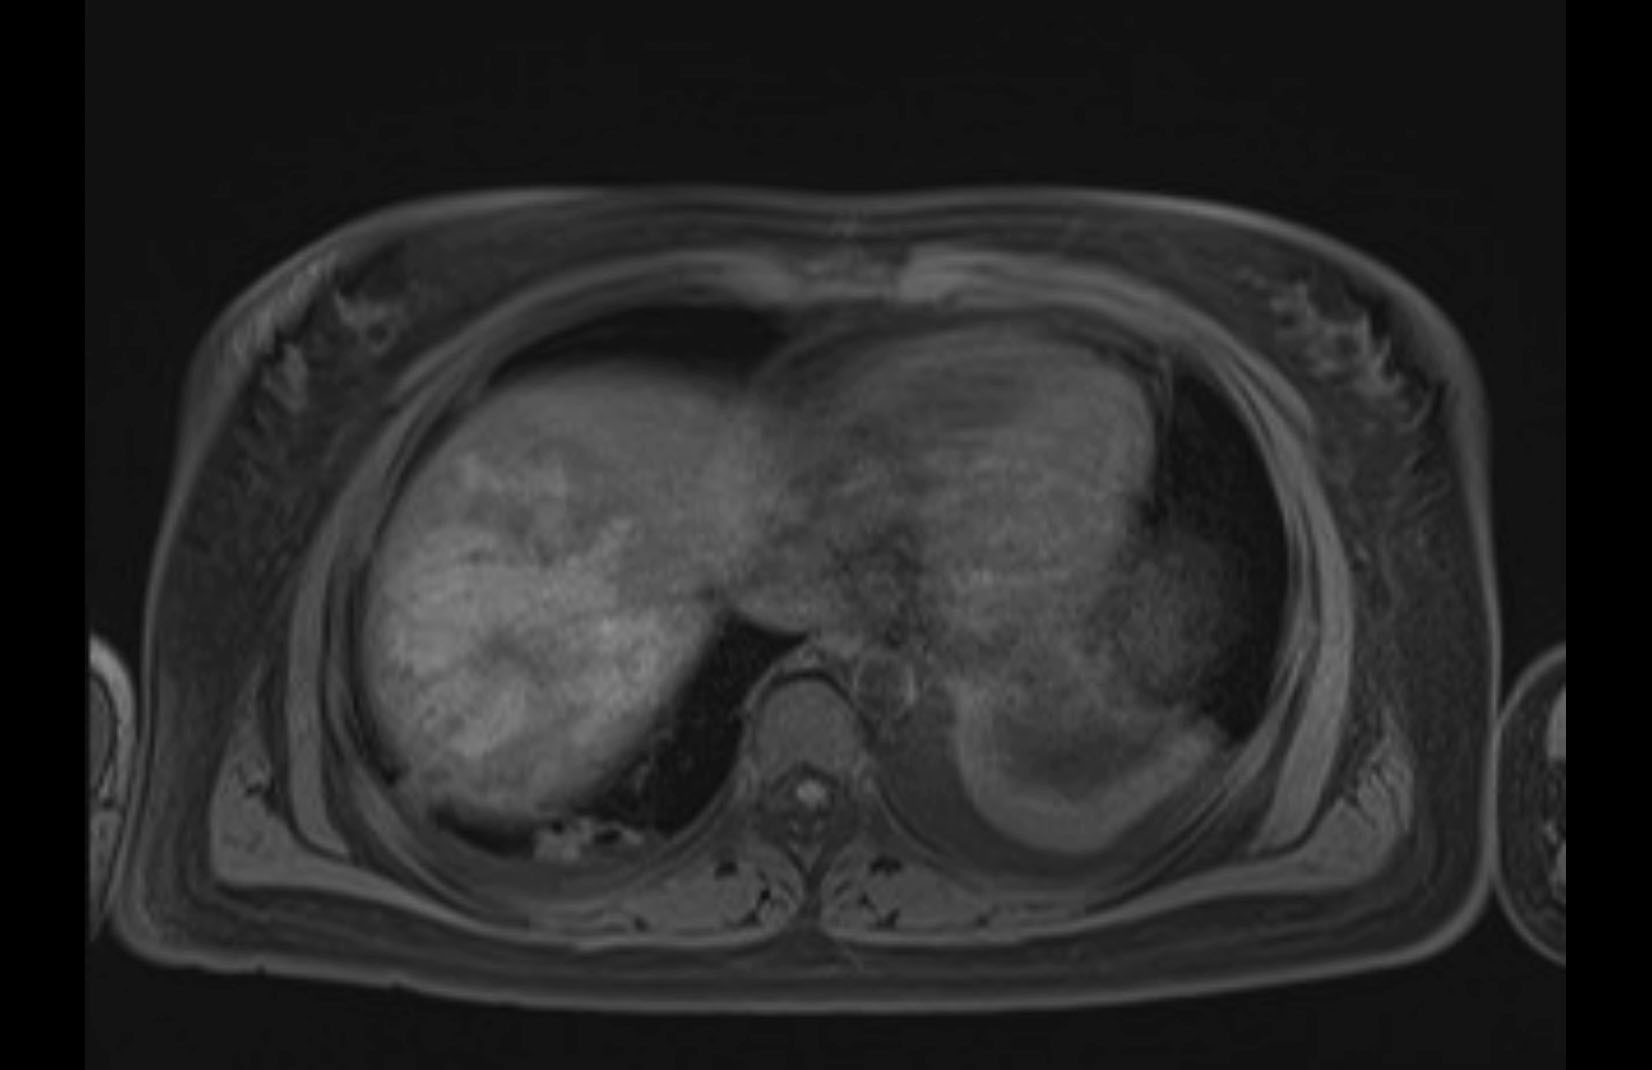

MRI T1

Imaging analysis

Based on initial findings, which issue(s) would you be most concerned about?